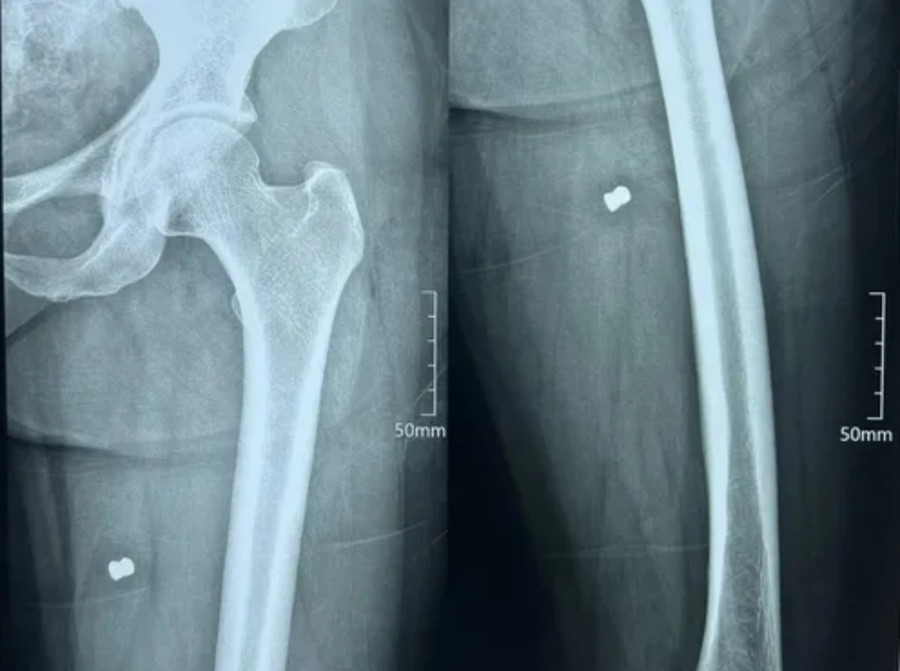

| Kim khí có hình thù giống đầu đạn găm bên trong chân của nữ công nhân Lê Thị Lưu. |

Ngay sau đó, hai nạn nhân được đưa đi cấp cứu tại Bệnh viện Đa khoa Phúc Hưng. Kết quả chụp phim cho thấy cả hai người đều có đạn trong đùi và bắp chân.